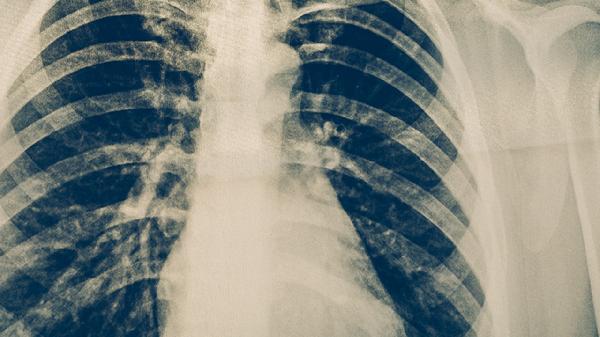

肺结核患者可遵医嘱使用异烟肼片、利福平胶囊、吡嗪酰胺片、乙胺丁醇片、链霉素注射液等抗结核药物。这些药物需联合使用以增强疗效并减少耐药性,具体用药方案应由医生根据病情制定。

肺结核患者应保证充足营养摄入,多食用高蛋白食物如鸡蛋、鱼肉,补充维生素丰富的蔬菜水果。避免吸烟饮酒,保持规律作息,治疗期间严格遵医嘱用药,不可自行增减药量或中断治疗。定期复查胸部影像学和痰菌检查,密切观察药物不良反应。